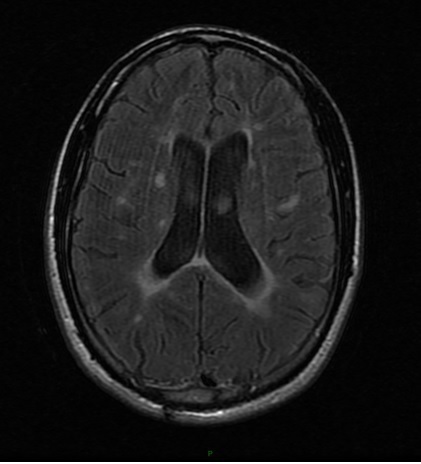

L’auxiliaire de vie vous a rapporté les résultats d’une imagerie par résonance magnétique (IRM) cérébrale réalisée il y a dix jours sur la prescription de son neurologue.

Question 7 : Parmi les propositions suivantes, laquelle (lesquelles) est (sont) exacte(s) ?

Les hypersignaux FLAIR sont dans la substance blanche (principale zone myélinisée du cerveau)

Il n’est pas possible de distinguer l’ancienneté d’une plaque sur les séquences FLAIR (la prise de contraste après injection de gadolinium permettra de confirmer qu’il s’agit d’une plaque active).

Les lésions observées sont donc compatibles avec le diagnostic de sclérose en plaques, mais leur ancienneté est inconnue et leur responsabilité dans les troubles de la vigilance du patient est très improbable.